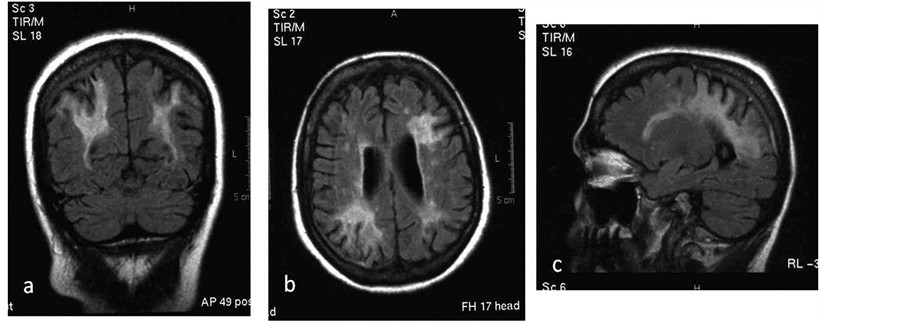

The first patient showed multiple lesions on both cerebral hemispheres, in the periventricular and subcortical white matter, in the splenium and on the left temporal lobe. Gadolinium was not used because of the presence of SLE nephritis (Figure 1). The DD could include MS or vascular disease.

Figure 1. (a) Coronal, (b) axial and (c) Sagital FLAIR sequences. MRI shows symmetrical extensive hyperintensity lesions in the periventricular, deep and subcortical white matter, also involving the splenium. Brain atrophy is incompatible with the patient’s age.